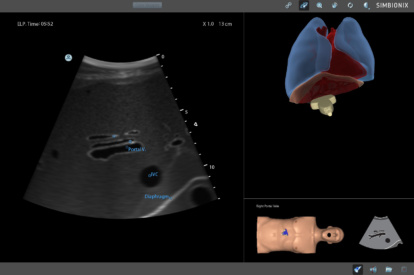

Ultrasound Mentor accelerates the development of basic to advanced technical and cognitive skills, by providing not only the probe manipulation training, but also a didactic environment enabling structured, self-guided learning including step-by-step instructions and educational aids such as 3D anatomical map and probe positioning assistant, all backed up with our progress monitoring tool MentorLearn.

- Step-by-step tasks provide a self-learning opportunity for sonography skills and scanning protocols

- Advanced diagnostic tools, including Color Doppler, CW, PW, M-mode, and measurements

Abdominal Module

Advanced Abdominal Module